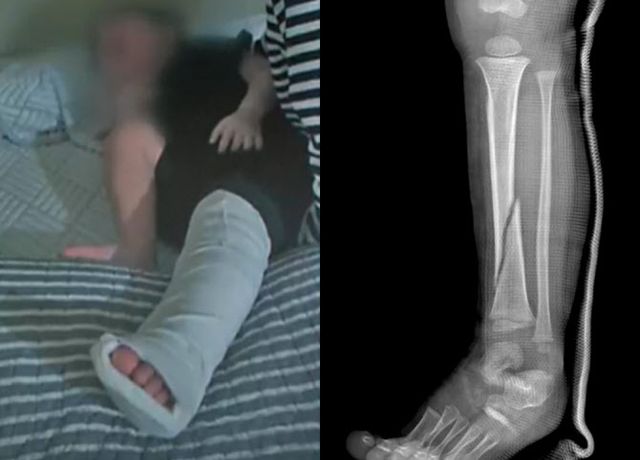

C씨가 도착한 뒤에야 B군은 인근 병원으로 이송되어 골절 진단을 받았고, 깁스를 한 채 어린이집으로 다시 돌아왔다.

A군 부모는 정확한 진단을 받기 위해 상급 병원으로 옮겼고 진단명은 ‘좌측 경골 몸통의 기타 골절, 폐쇄성’이었다. 왼쪽 정강이의 굵은 뼈가 부러져 발목 쪽으로 밀려 내려갔고 전치 14주의 치료가 필요했다.

D씨는 “의사가 ‘어떤 힘으로 눌렀기에 이렇게 큰 뼈가 부러지냐’고 물었다”며, “성인이 된 후에도 절뚝거릴 수 있다는 말을 듣고 하늘이 무너지는 기분이었다”고 호소했다.

B군은 약 2주간 입원 치료를 받은 뒤 깁스를 한 채 통원 치료를 이어가고 있다. A씨는 사건 직후 어린이집을 퇴사한 것으로 알려졌다.